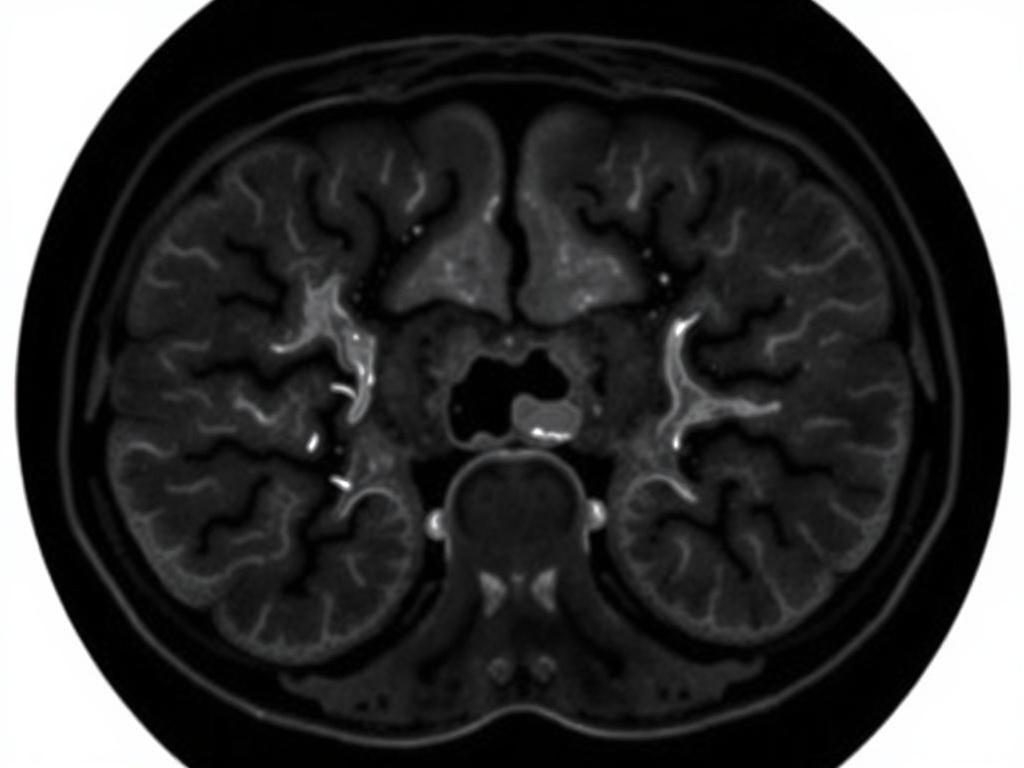

Компьютерная томография (КТ) с контрастом стала одним из важнейших методов в диагностике множества заболеваний. Это высокоточная процедура, позволяющая визуализировать внутренние органы и их структуры, а также осматривать сосудистую систему. Одной из специфических областей применения КТ является изучение состояния здоровья брахиальной аорты и артерий нижних конечностей, что позволяет существенно повысить точность диагностики.

Контрастные вещества вводятся в организм для улучшения визуализации исследуемых зон. Это необходимо для того, чтобы обеспечить четкость изображения сосудов и окружающих тканей. При проведении мскт ангиографии брюшной аорты и артерий нижних конечностей контраст позволяет выявлять заболевания, такие как атеросклероз, тромбообразование и опухоли. Введение контрастного вещества помогает врачам судить о состоянии кровообращения, стентирования и необходимости хирургического вмешательства.